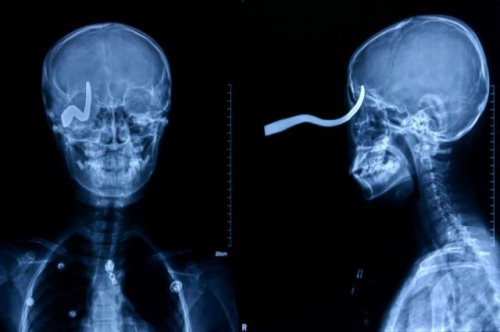

По множественным сообщениям международной прессы, 11-летний китайский школьник Лю Чеонь (Liu Cheong) столкнулся со смертью, когда его друг выстрелил ему в голову 40-сантиметровой стрелой. Стрела вошла в его череп через глазницу и застряла в голове. Каким-то чудом мальчик избежал смертельной мозговой травмы.